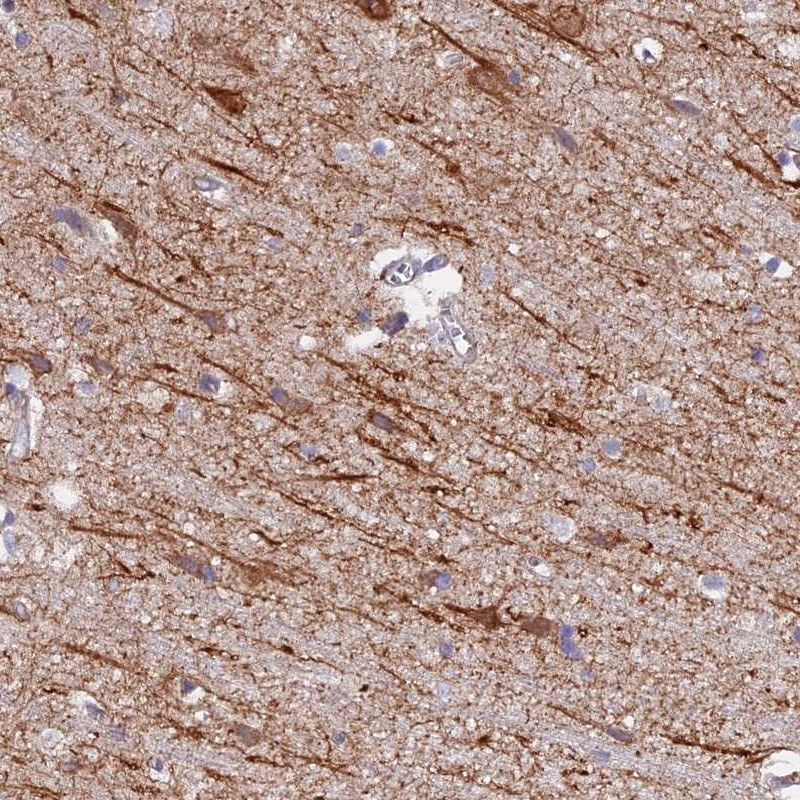

Immunohistochemical staining of human cerebral cortex shows distinct cytoplasmic positivity in subsets of neuronal cells.